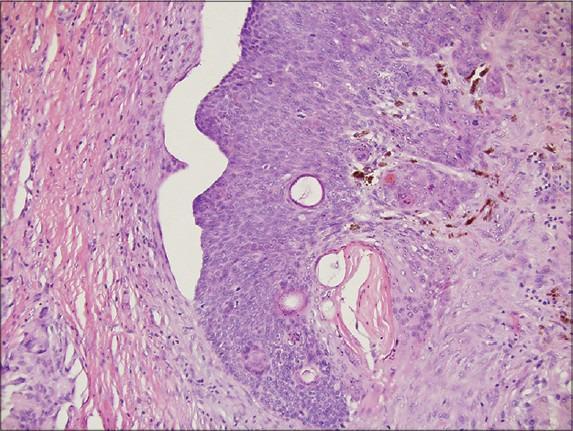

An unusual cystic lesion on the helix.

https://cdn.ncbi.nlm.nih.gov/pmc/blobs/36fc/4144225/9f42eef5188c/IDOJ-5-326-g001.jpg